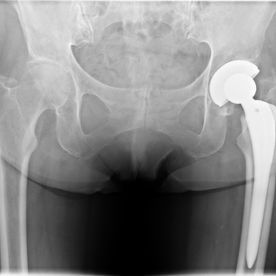

Bei fortgeschrittenen Hüftgelenkverschleißbeschwerden (Koxarthrose), die trotz Ausschöpfung der konservativen Behandlungsmöglichkeiten (z.B. Gabe von knorpelregenerativen Spritzen in das Gelenk-> Hyaluronsäure/thrombocytenreiches Eigenblutplasma, manualmedizinischer Lockerung von Gelenkkapseln) Beschwerden wie Belastungsschmerzen verursachen, ist es möglich, das schmerzhafte Hüftgelenk operativ zu ersetzen. Über einen relativ kleinen operativen Zugangsweg werden die verschlissenen Gelenkkomponenten entfernt und durch langjährig bewährte Implantate ersetzt, die zu 99% zementfrei im Knochen verankert werden.

Derartige Eingriffe werden regelmäßig von

Dr. Prange in der Paracelsus Klinik Hannover-Langenhagen unter stationären Bedingungen durchgeführt. Der Krankenhausaufenthalt dauert zumeist eine Woche, im Anschluss daran folgt eine stationäre Rehabilitationsbehandlung über 3–4 Wochen in einer entsprechenden Reha-Klinik.

Hüftprothese